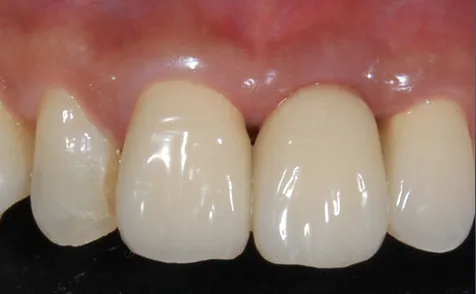

インプラントが安定したことを確認してから最終的な人工歯を装着するとともに、色が気になっていた両隣の被せ物も作り直しました。被せ物の材質には、自然な白さで適合性も良い「セラミック」を使用しています。

ご自身の歯と馴染んだ自然な仕上がりになり、噛み合わせも問題ありません。

患者様にも「鏡の前でじっくり眺めてもどの歯を治したかわからないほど綺麗。口元のコンプレックスが解消されたので、以前よりも思い切り口を開けて笑えるようになった」と大変お喜びいただきました。